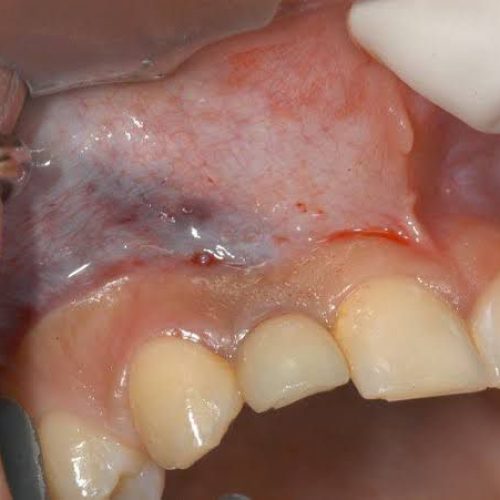

2. Receding gums or gum recession:

Gingival recession is also one of the main complications faced by a person after getting an implant. Recession of the gums at the site of the implant occurs if oral hygiene is not maintained. To prevent receding gums, the patient should maintain their oral hygiene properly and visit their dentist for regular check-ups.